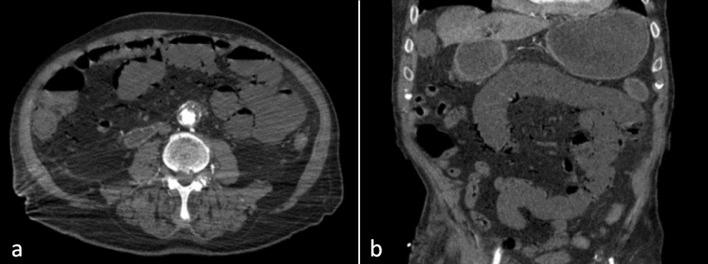

Acute Mesenteric Ischemia (AMI) is a rare life-threatening entity caused by sudden interruption of the blood supply to a segment of the bowel due to impairment of mesenteric arterial blood flow or venous drainage. Clinical presentation varies according to the time course of vascular occlusion. Contrast-enhanced Computed Tomography (CT) of the abdomen represents the main diagnostic test for AMI diagnosis, enabling fast and excellent evaluation of the intestine, mesenteric vasculature, and other ancillary characteristics of AMI. Typical CT findings of AMI include paralytic ileus, decreased or absent bowel wall contrast-enhancement, pneumatosis intestinalis, and porto-mesenteric venous gas. We hereby report a case of an 89-year-old man presenting with AMI due to Superior Mesenteric Artery (SMA) thrombotic occlusion following endovascular stenting superficial femoral arteries. Typical findings were observed on abdominal CT imaging, yet associated with the presence of gas exclusively in the SMA district, without any involvement of the porto-mesenteric venous system. Different imaging features and pitfalls can help radiologists to accurately diagnose AMI, especially when irreversible bowel damage is about to occur. Therefore, radiologists and emergency physicians should be aware of the unusual association between gas in the SMA arterial district and AMI, even in the absence of porto-mesenteric venous system involvement, in order to urge prompt surgical consultation when observed.

急性肠系膜缺血(AMI)是一种罕见的危及生命的病症,由肠系膜动脉血流或静脉引流受损导致肠段血液供应突然中断引起。临床表现根据血管闭塞的时间进程而有所不同。腹部增强计算机断层扫描(CT)是诊断AMI的主要检查方法,能够快速且出色地评估肠道、肠系膜血管系统以及AMI的其他辅助特征。AMI的典型CT表现包括麻痹性肠梗阻、肠壁强化减弱或消失、肠壁积气以及门静脉-肠系膜静脉积气。我们在此报告一例89岁男性患者,因股浅动脉血管内支架置入术后肠系膜上动脉(SMA)血栓形成闭塞而出现AMI。腹部CT成像观察到典型表现,但仅在SMA区域存在气体,门静脉-肠系膜静脉系统未受累。不同的影像学特征和陷阱有助于放射科医生准确诊断AMI,尤其是在即将发生不可逆肠损伤时。因此,放射科医生和急诊医生应意识到SMA动脉区域气体与AMI之间的异常关联,即使在门静脉-肠系膜静脉系统未受累的情况下,以便在观察到这种情况时促使及时进行外科会诊。